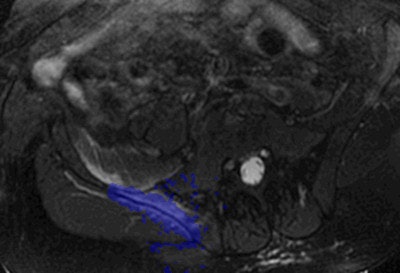

Some methods allow totally noninvasive treatment. This is the latest trend: intervention without needles or catheters in, for instance, the treatment of uterine fibroids. These benign uterine tumors can be treated with focused ultrasound (FUS). The ultrasound waves are concentrated to produce heat within a focal point. To treat uterine fibroids, the ultrasound waves are applied via an ultrasound source in the MRI table, MRI being used as an imaging procedure to locate the fibroids and to measure the development of the temperature within the fibroid and surrounding tissues during treatment.